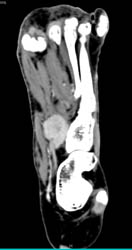

DIEP Flap Planning